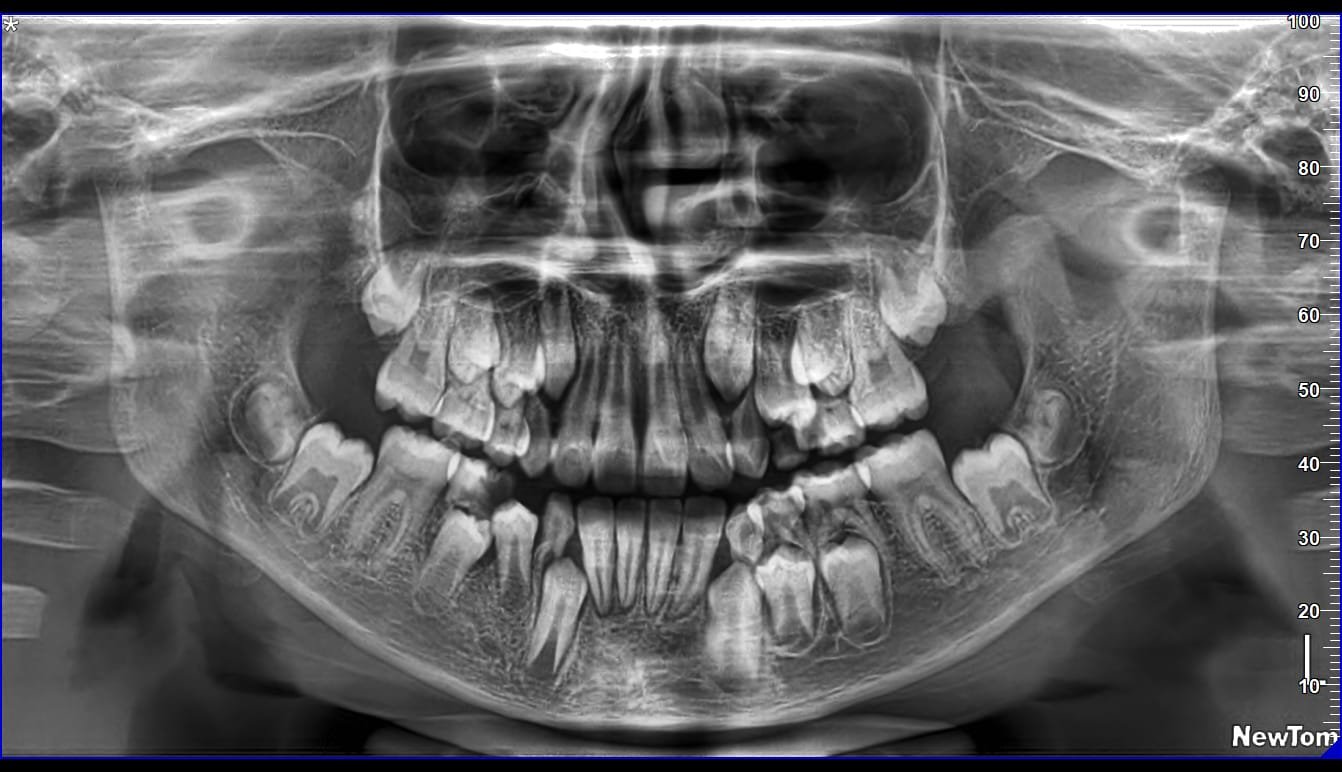

He is certified in Cone Beam Computed Tomography (CBCT) and has extensive experience in advanced radiological diagnosis. Dr. Singh is associated with several reputed centers across India as a consultant radiologist for CBCT reporting. His expertise includes implant planning, impacted teeth localization, oral and maxillofacial pathology interpretation, TMJ assessment, maxillary sinus evaluation, and airway analysis.

Full Mouth CBCT 3500/-

CBCT Maxillary Sinuses 2000/-